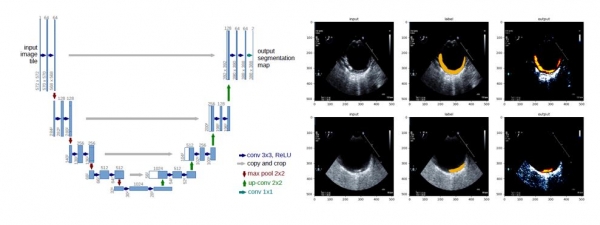

유넷모델을 이용한 플라크 영역 예측 사례

연구팀은 머신러닝의 다양한 기법 중 오토엔코더(Autoencoder)와 유넷(U-net)모델을 대동맥벽의 초음파 영상 판별에 적용했다. 대동맥벽을 초음파 영상으로 판별하면 뇌졸중의 원인으로 떠오르고 있는 대동맥 동맥경화성 플라크의 상태를 확인할 수 있다.